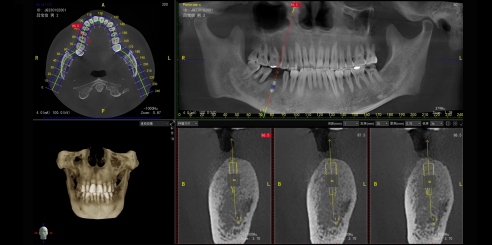

Simulación de Implantes

Puede evaluar la calidad y la cantidad de hueso del área del implante y delinear automáticamente el tubo neural. Aclarar la relación entre la posición del implante y la estructura anatómica adyacente para seleccionar con precisión la posición del implante, la longitud óptima y el diámetro del implante. Puede mejorar la tasa de éxito y evitar posibles daños a los nervios o vasos sanguíneos.

Reconstrucción combinatoria multiplanar (MPR)

En el software SmartVPro se pueden observar simultáneamente las imágenes horizontales, corales y sagitales. También es posible realizar cortes de la tomografía en cualquier posición. Al mismo tiempo, se obtienen cortes bucoglosales y mesiales distantes para facilitar el diagnóstico.

Medición de Densidad

Evaluación visual de la calidad ósea, aportando mayor comodidad a los dentistas.